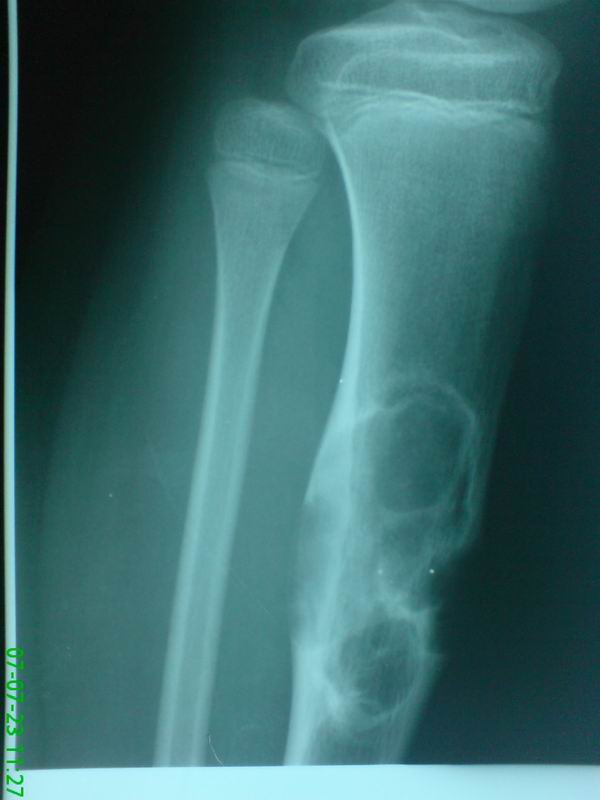

标题: PED0280:女性,10岁,左小腿无诱因疼痛,一般状况良好,无发热乏 [打印本页]

标题: PED0280:女性,10岁,左小腿无诱因疼痛,一般状况良好,无发热乏

骨破坏区呈多房样改变,邻近骨皮质变薄并偏心性膨出,考虑1。软骨瘤2。骨巨

胫骨骨干增粗,骨皮质呈膨张性改变。髓腔扩大,其内有多个圆性低密度影,且有长短不一的骨瘠影。邻近骨质硬化。外围骨皮质部分消失。考虑软骨粘液样纤维瘤可能性大。

胫骨中上段多房囊肿,呈蜂窝状向外膨胀,囊内含有粗细不等的房间隔,偏心性生长。考虑良性骨肿瘤----1软骨粘液性纤维瘤。2骨化或非骨化性纤维瘤。

软黏纤>骨化性纤维瘤。髓腔侧硬化明显,边缘扇形,大囊套小囊,皮质偏心膨胀,分隔粗细不等,无明显钙化,首先考虑软黏纤,年龄及病变部位也相符。骨化性纤维瘤可有类似改变,其他不考虑。